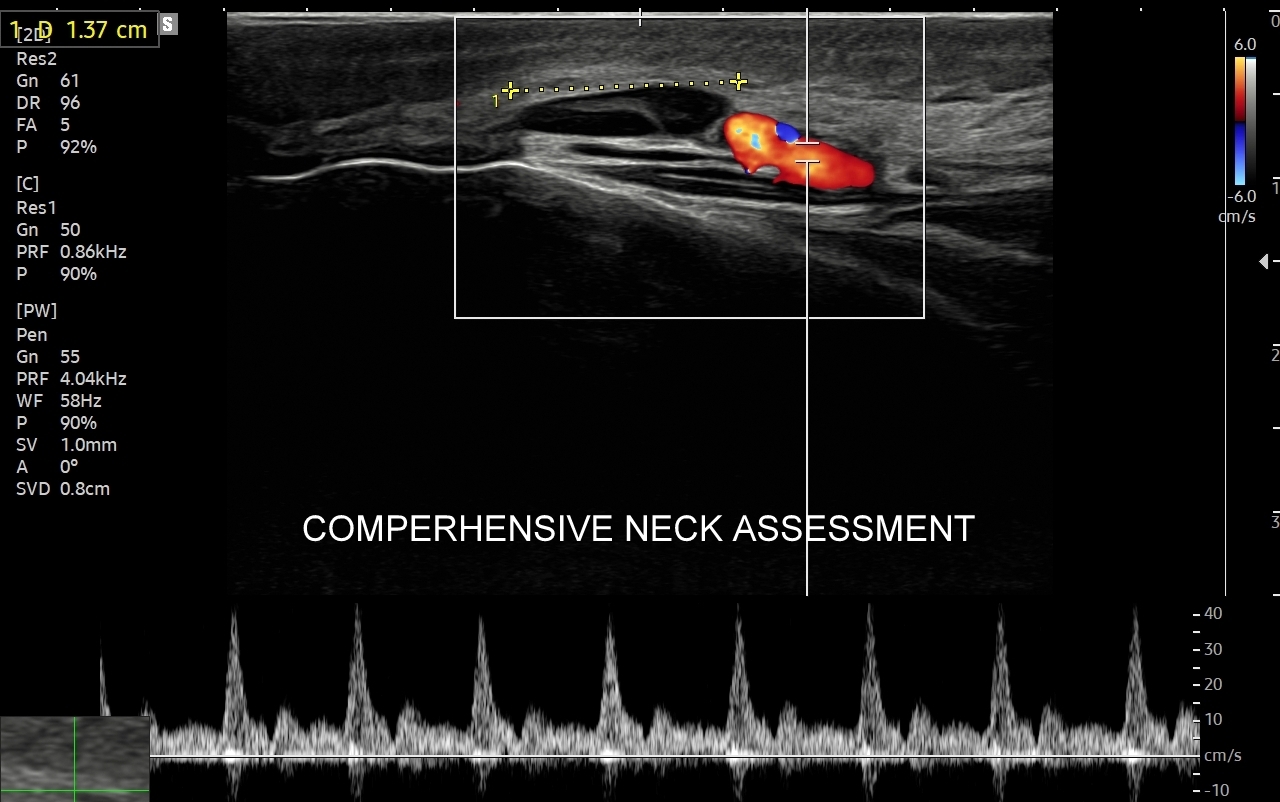

Badanie USG jest podstawową metodą obrazowania węzłów chłonnych. W jego trakcie ocenia się nie tylko wielkość węzłów, lecz także ich kształt, proporcje wymiarów, morfologię, czyli wygląd zewnętrzny oraz strukturę wewnętrzną, ich unaczynienie, spoistość, a także tkanki otoczające. W trakcie interpretacji badania pod uwagę bierze się również zbierany od pacjenta wywiad chorobowy oraz wyniki innych badań obrazowych i laboratoryjnych takich jak morfologia, OB, CRP, żelazo, ferrytyna, TIBC, innych parametrów infekcyjnych, a także onkologicznych. Ultrasonografia węzłów chłonnych jest procedurą bezpieczną i dokładną. W Pracowni dr Szczepańskiego węzły chłonne oceniane są nowoczesną metodą MPUS (multiparametryczne badanie USG), w szczególności z zastosowaniem trybów mikrounaczynienia i elastografii.

USG węzłów chłonnych szyi i karku

Do powiększenia węzłów chłonnych szyi, stanu określanego jako limfadenopatia, dochodzi najczęściej w przebiegu chorób zakaźnych górnych dróg oddechowych, wirusowych i bakteryjnych. Inne przykłady przyczyn limfadenopatii szyjnej obejmują ropne choroby zębów, migdałków i zatok przynosowych; odczyny w chorobach autoimmunologicznych, np. w chorobie Hashimoto i Sjögrena; a także rozrostowe schorzenia układu hematologicznego (białaczki i chłoniaki) i choroby nowotworowe jak np. rak tarczycy, krtani, migdałka, czy języka. Należy mieć na uwadze, iż w przypadku podejrzenia chorób układu krwiotwórczego oraz mononukleozy zakaźnej, oprócz węzłów chłonnych, niezbędne jest również badanie USG wątroby i śledziony. W części przypadków, gdy podejrzewa się możliwość choroby nowotworowej lub w celu jej wykluczenia, lekarz może zalecić rozszerzenie diagnostyki obrazowej na inne obszary ciała.